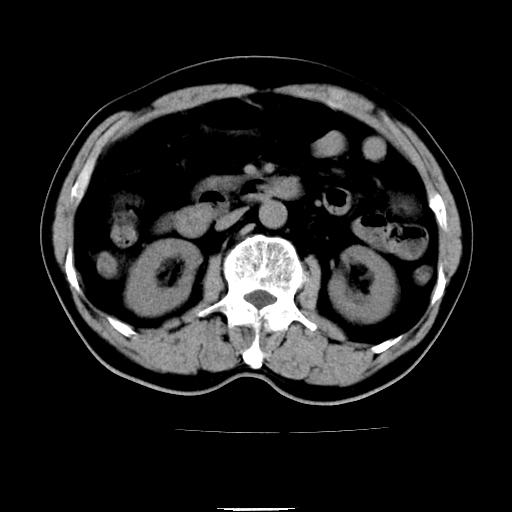

以下是引用chenqiong在2010-3-25 20:56:00的发言:[br]1、胆囊炎,胆囊息肉[br]2、肝内胆管及胆总管扩张,胆总管下端结石[br]3、十二指肠乳头旁憩室

以下是引用zxl51642在2010-3-26 10:47:00的发言:[br]胆囊炎,胆囊息肉,胆总管扩张,但未看到明显肿块,肝内胆管扩张不像恶性,炎性狭窄或阴性结石可能吧,建议mrcp,右肾小囊肿